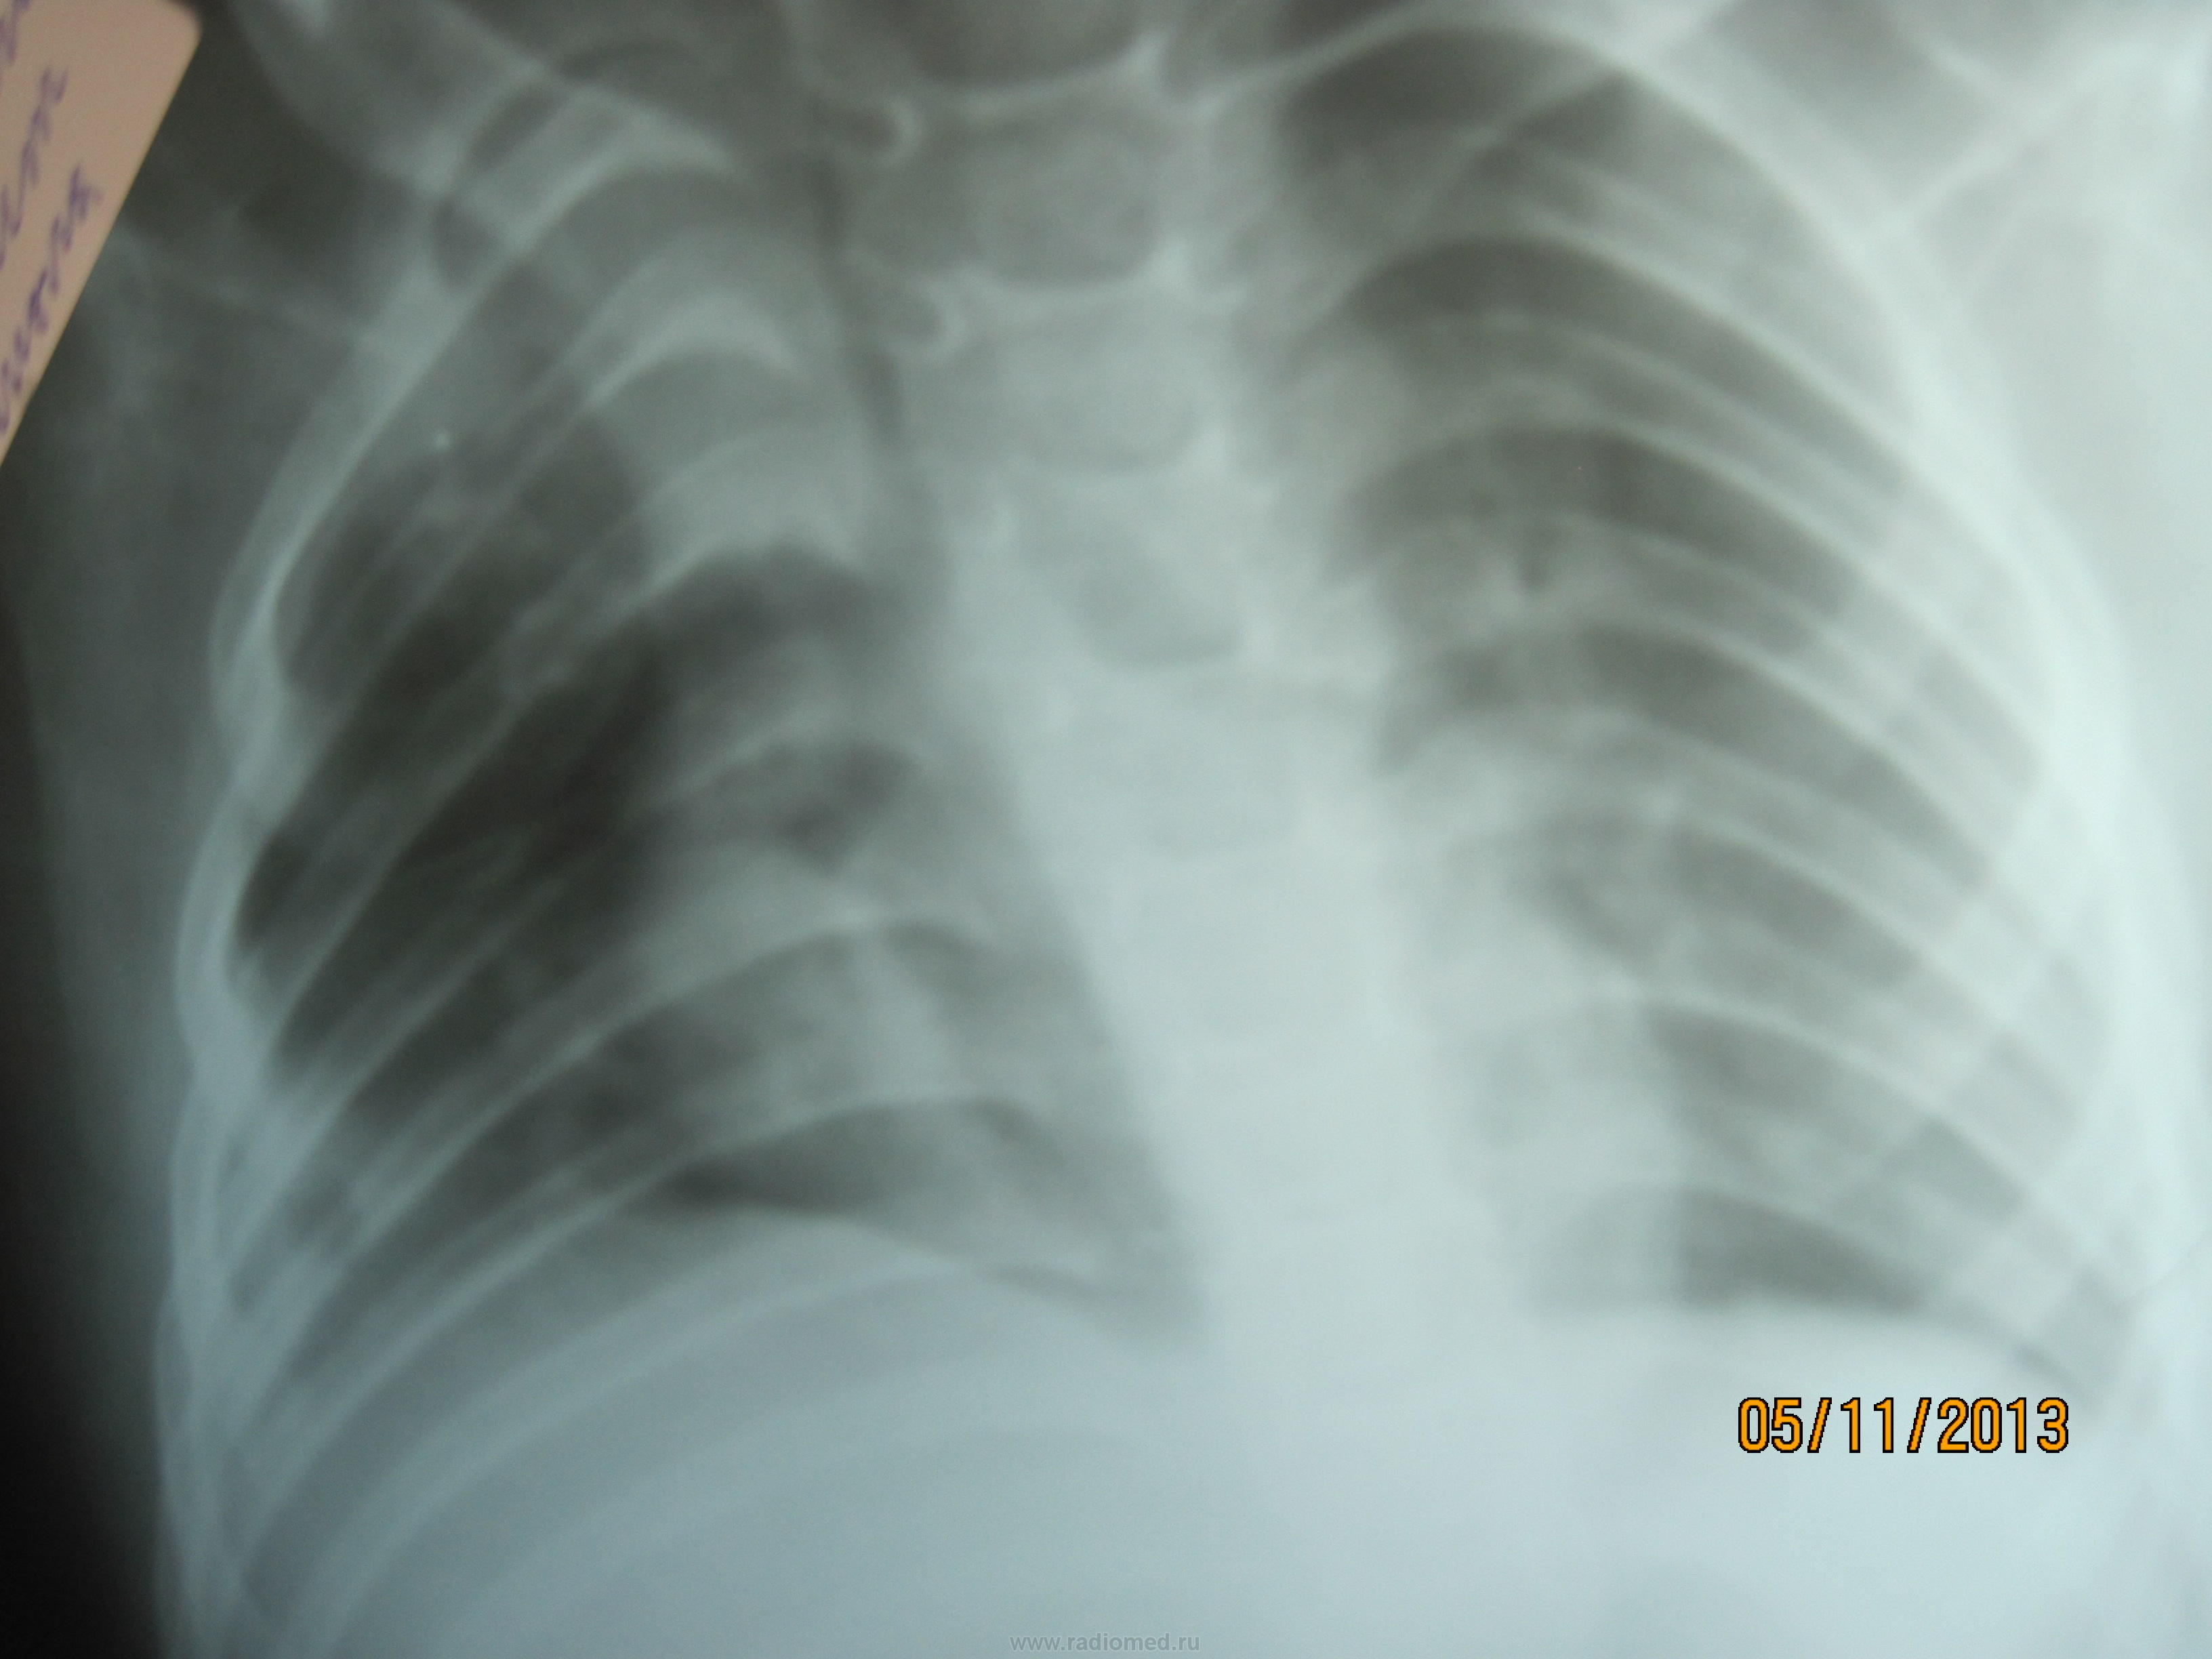

Что скажите по последнему снимку??? Что с этим ребенком делать не знает никто...Чем лечить и куда направлять тоже...

Cредостение на месте. Написала инфильтрация S1, 2, 3, 5 Пневмония без динамики. Завтра снова хотят контроль делать и рентгена и УЗИ.

аспирация не исключена